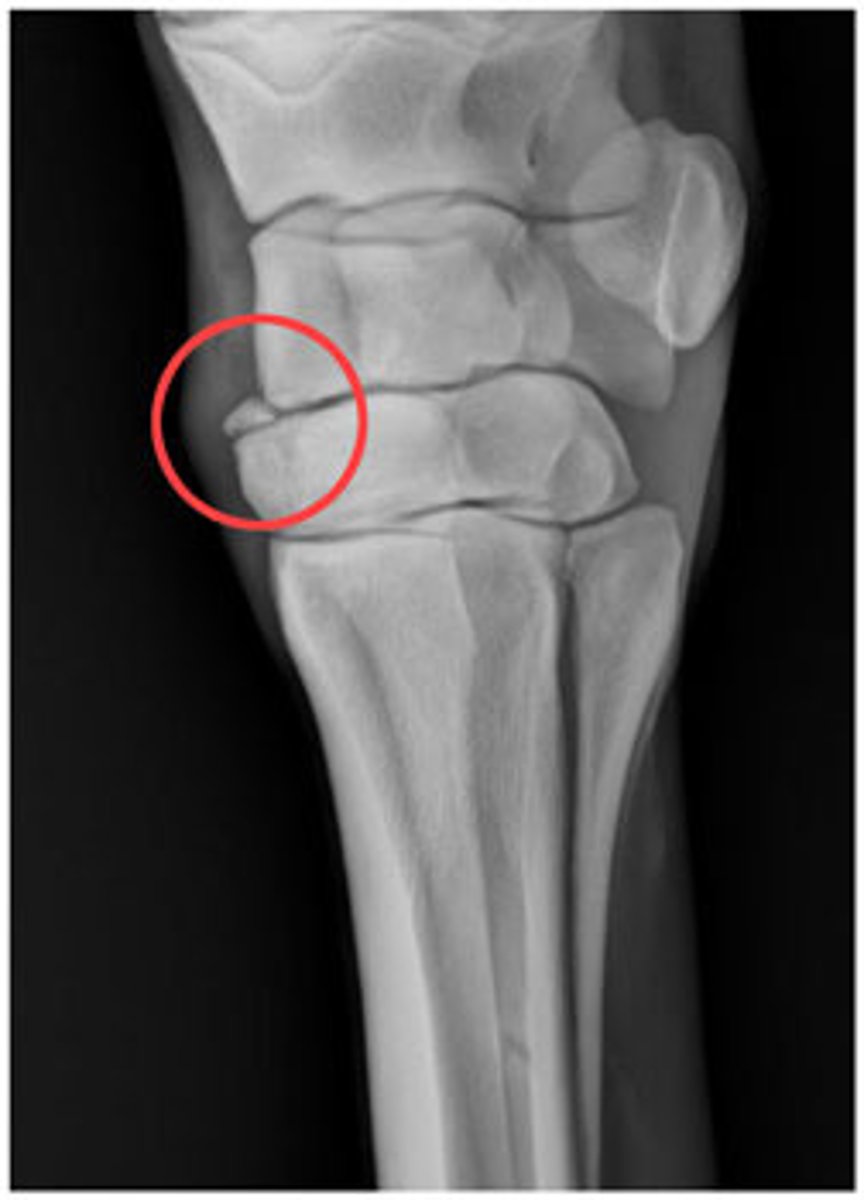

Fracture of proximal half of ulna with dislocation of radial head

Monteggia fx

Intraarticular fracture of radial styloid process. Also called a chauffeur's fracture.

Hutchinson's fx